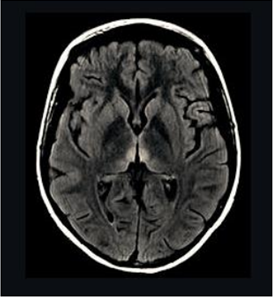

Mulher de 22 anos chega ao pronto atendimento com história de dificuldade para caminhar por falta de equilíbrio há três meses. Evoluiu com piora gradual e hoje deambula somente com apoio. O marido relatou que a paciente realizava atividade física por várias horas diariamente, abandonando a prática devido ao quadro clínico, e que fazia dieta constantemente. Ao exame clínico: paciente muito emagrecida, IMC 16, taquicárdica, sonolenta, com ataxia de marcha, desorientada no tempo e no espaço e com alteração na motilidade ocular extrínseca. A paciente foi internada para investigação. Dois dias após, apresentou piora e foi transferida para a UTI, em coma. A imagem da ressonância magnética de crânio evidenciou a alteração exemplificada pela imagem ao lado e o exame de liquor foi normal. Em relação ao caso apresentado, é correto afirmar:

Enunciado 1991671-1